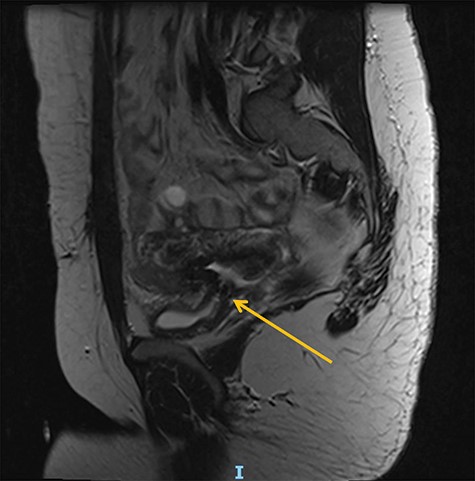

A 25-year-old woman was referred from a secondary hospital following a major uterine rupture at 40 + 6 gestation resulting in stillbirth and bladder injury. She was expected to deliver by vaginal birth after caesarean as she already had one child that was delivered by straightforward C-section. Labour was induced at 40 weeks due to high blood pressure, but during this process, the patient reported a tearing sensation in her lower abdomen and was taken to theatre for an emergency C-section and was discovered to have a uterine rupture and intrauterine foetal death. The C-section resulted in bladder injury and right ureteric transection. Subsequently, she developed a residual vesicovaginal fistula associated with ureteric obstruction at the level of the repair, and required nephrostomy and indwelling catheter drainage (Figures 1 and 2).

At a 1-year follow-up, the patient was complaining of flank pain, so an technetium-99m mercaptoacetyltriglycine renography (MAG3) was performed, showing good drainage but mild to moderate reflux into the reimplanted ureter. Normal bladder and sexual function were restored, and she was discharged from routine follow-up after 18 months. Following successful conception, she had a specialist obstetric review and was planned to have an elective C-section at between 37 and 38 weeks to avoid labour. Unfortunately, she had a premature vaginal delivery due to chorioamnionitis at 23 + 4 gestation complicated by sepsis with features of shock from which she and her baby made a full recovery (Figs. 1 and 2).

Preoperative MR abdomen, transverse plane. Arrow indicating obstructed right ureter